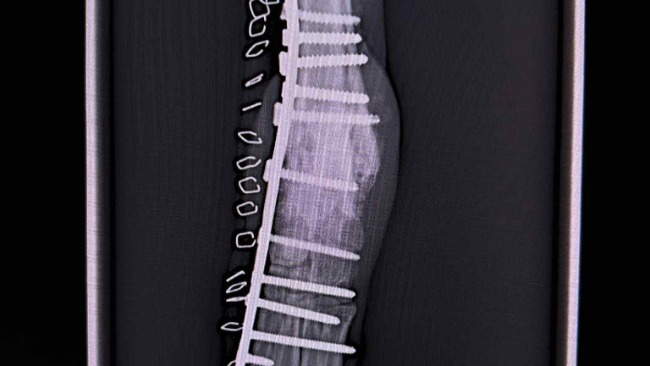

Niedawno Zenek przeszedl ciezka operacje artrodezy ,ratujaca jego łapke .Koszt operacji wyniosl 10tys,dzieki temu ma szanse ocalic lapke i zyc bez bolu .

Niestety Zenek nadal potrzebuje wsparcia ,puscila jedna ze srub ,znowu operacja i dalsze koszty .Prosze pomozcie